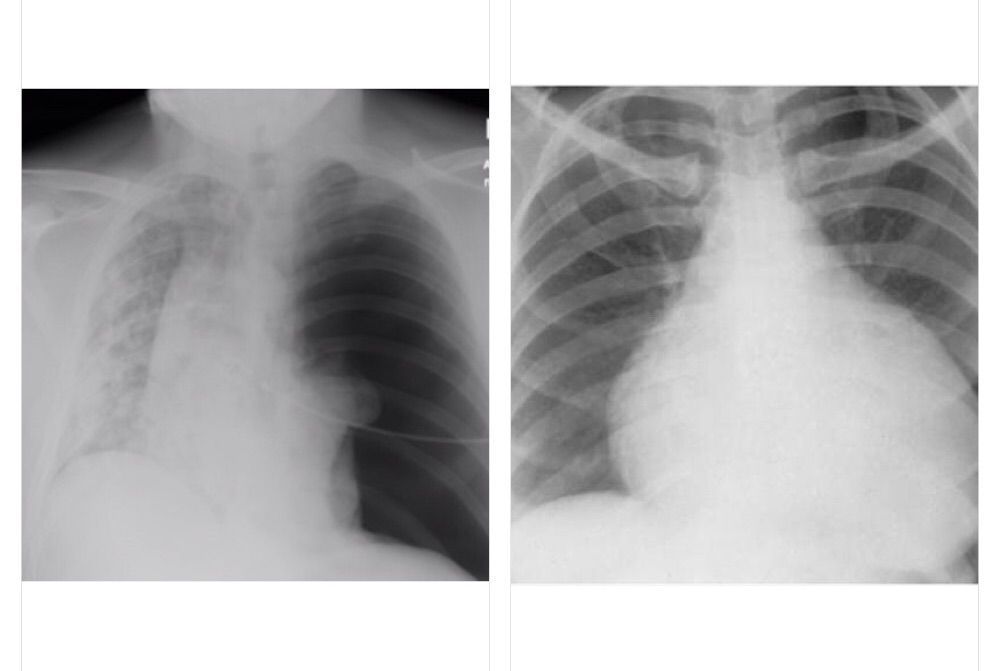

Above left is a X-ray of tension pneumothorax.you can appreciate the air accumulation which is darker area there.it’s mostly of penetrating trauma rather blunt injury. A life threatening event ,caused by accumulation of air the pleural space due to breach in the 🫁 surface(stab injury),medical ,surgical causes.this breach act as a one way -which leads to positive pressure accumulation-shifting mediastinum to other side.Needle decompression f/b tube thoracostomy in the 2nd IC space midclavicular line is the management. Above right side is the X-ray of cardiac tamponade -medical emergency-due to accumulation of blood ,fluid in the pericardial space due to chest trauma, aortic rupture,TB,cancer,pericarditis,MI,etc.. immediate drainage should be done.-pericardiocentesis(subxiphoid -for unstable patients).immediate radio confirmation and Echo is required. clinically both may look similar but we can differentiate. T-pneumothorax:— 1.no breathe sounds (hyper resonance on percussion)2.increased JVP 3.hypotension. Cardiac tamponade:—1.muffled heartsounds 2.increased JVP 3.hypotension{BECKS TRIAD}.